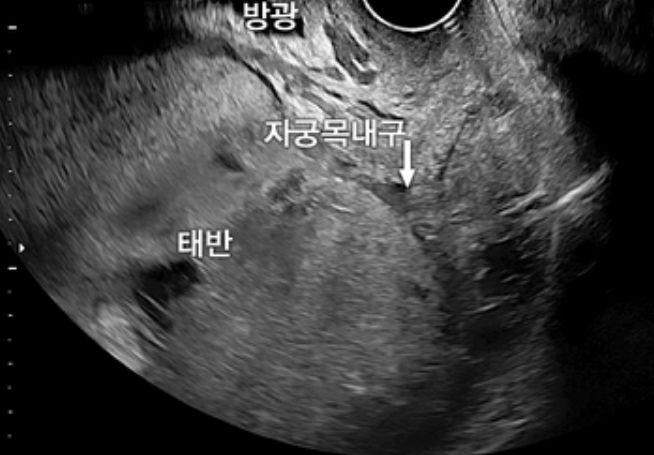

Imp: 전치태반(placenta previa)

• 초음파상 태반이 자궁목내구를 덮고 있는 전치태반이 확인된다.

• 옥시토신: 전치태반일 경우 질분만의 금기로, 분만시 반드시 제왕절개를 시행한다.